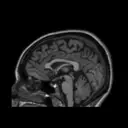

Our research explores the neurobiological basis of addiction (tobacco, alcohol, marijuana) and mood/anxiety disorders (depression, bipolar disorder, and PTSD). We use state-of-the- art brain imaging technologies Positron Emission Tomography (PET) and Magnetic Resonance Imaging (MRI) to investigate certain receptors in the brain and neural mechanisms that are thought to underlie these disorders. Taking part in our research will improve our understanding of addiction and mood disorders so that they can be treated more effectively in the future.